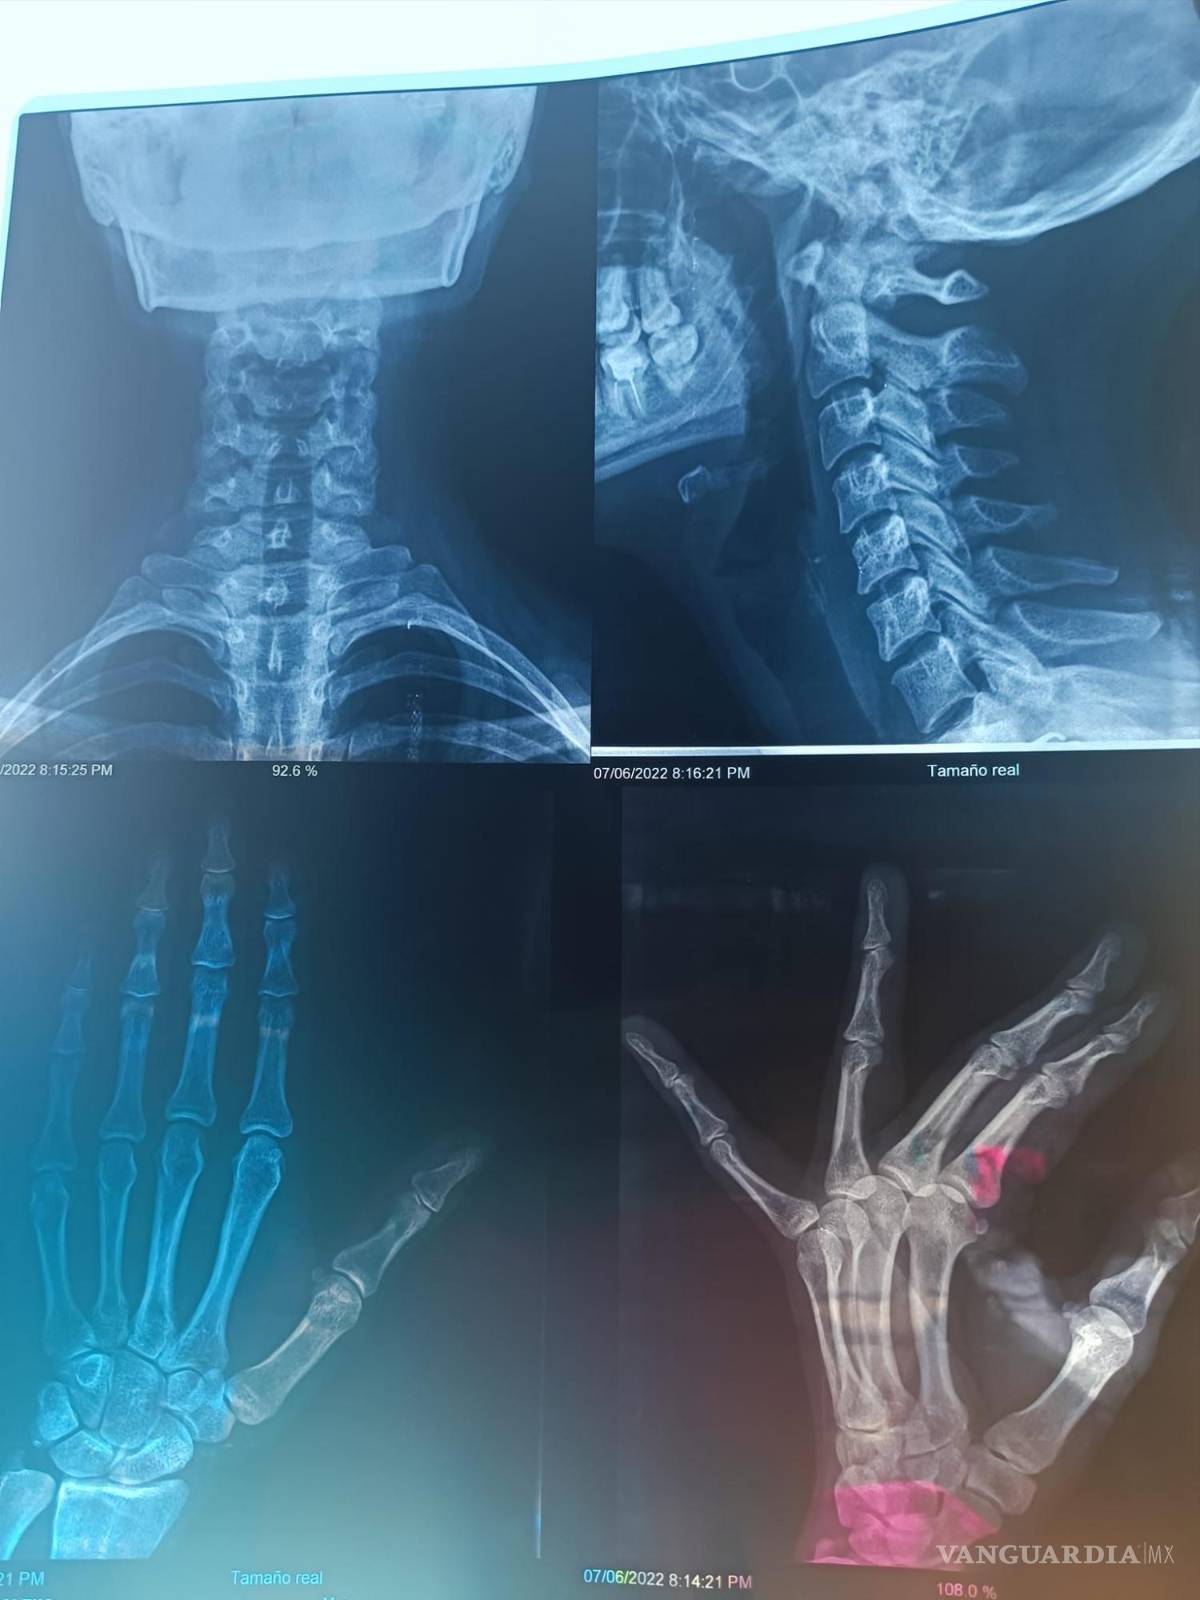

“Una prima mía y su esposo se subieron a mi coche y me comenzaron a golpear, dejándome diferentes lesiones que son las que se pueden ver en las fotos.

“La cosa llegó a tanto, que me golpearon en la nariz, cosa que hacía que yo batallara para respirar. Aparte que el esguince en el cuello me complicaba las cosas, hasta para comer”, expresó Alexa.

Con base al testimonio, declaró que la agredieron haciendo uso de cinturones y cadenas en las manos, lo que infligió más daño y causó lesiones severas que se vieron reflejadas durante la revisión médica de la víctima, además de esguinces en los dedos y torceduras en la nariz.

$!Imagenes de las radiografías de Alexa.